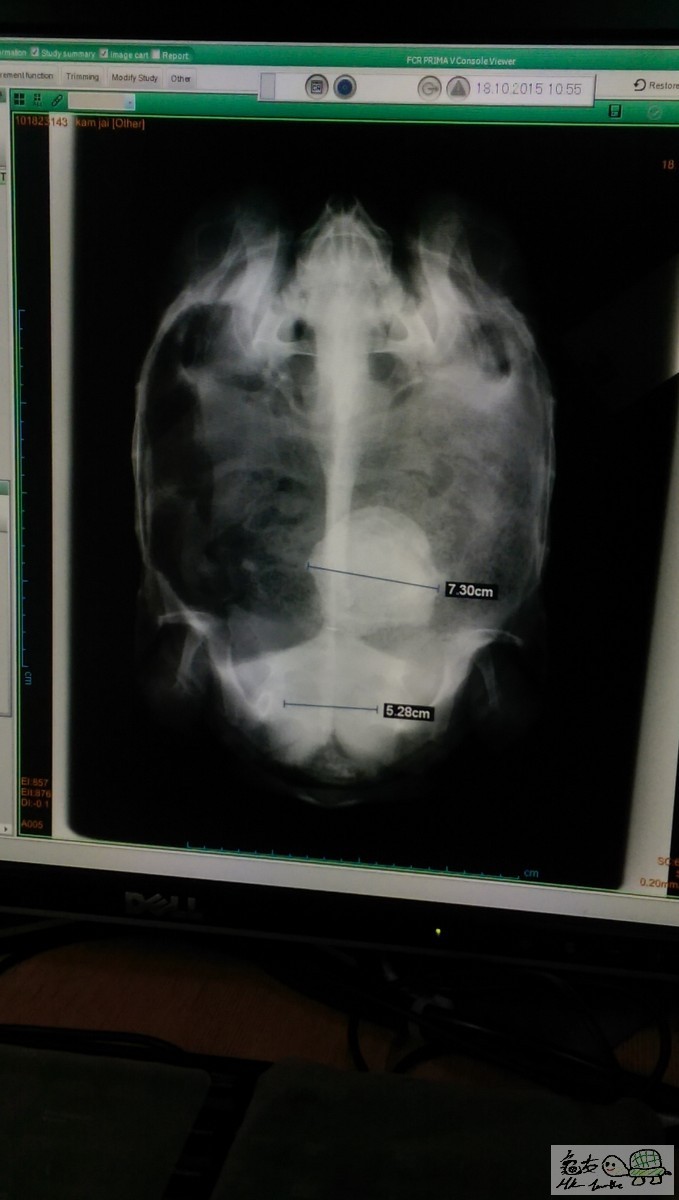

養左5年GE盾腎龜剛剛去睇完獸醫, 發現有粒都幾大GE結石係入面

醫生話除左做手術都無辨法 , 但係做完手術後復原GE成功率唔高........所以都唔想比佢做......

做完手術不足4成機會好返

你隻龜要做手術都應要預二萬左右

佢小便有血,所以走去睇LO.......

因為咁大粒石己形成左, 食乜都溶解唔到

除非你粒石可以去到肛門位.